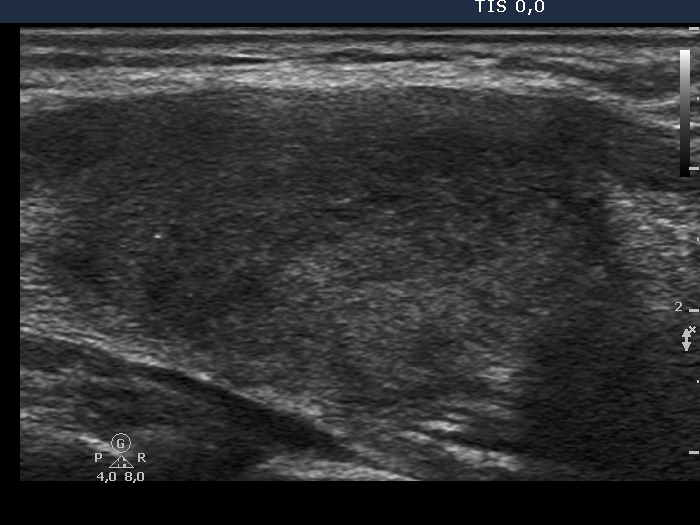

A very typical presentation of de Quervain's thyroiditis is demonstrated with the ill-defined hypoechogenic areas causing a cloudy appearance and with decreased vascularization. |

Final diagnosis: de Quervain's thyroiditis.

We had the patient stop the thyrostatics and a 6-week steroid therapy was started which resulted in prompt amelioration of neck complaints.

2 weeks later the FT4 level was 16.0 pM/L. 2 years after discontinuation of steroid the patient is free of complaints and the US had normalized. |